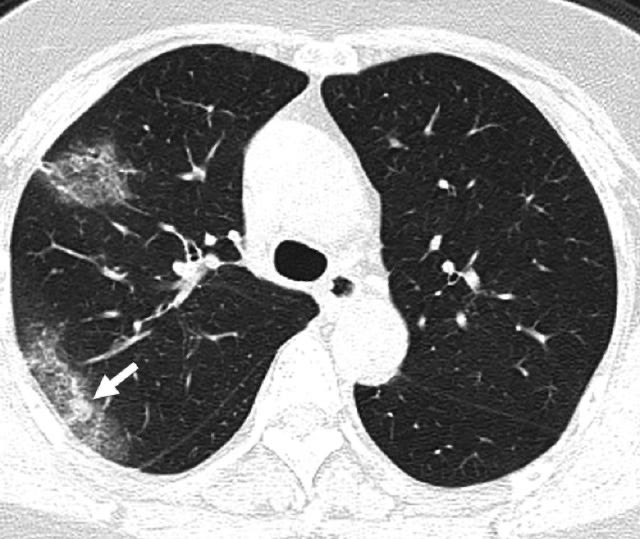

Scans from a 27-year-old woman who worked in Wuhan showed a "ground-glass halo" — white patches that surround a small nodule.